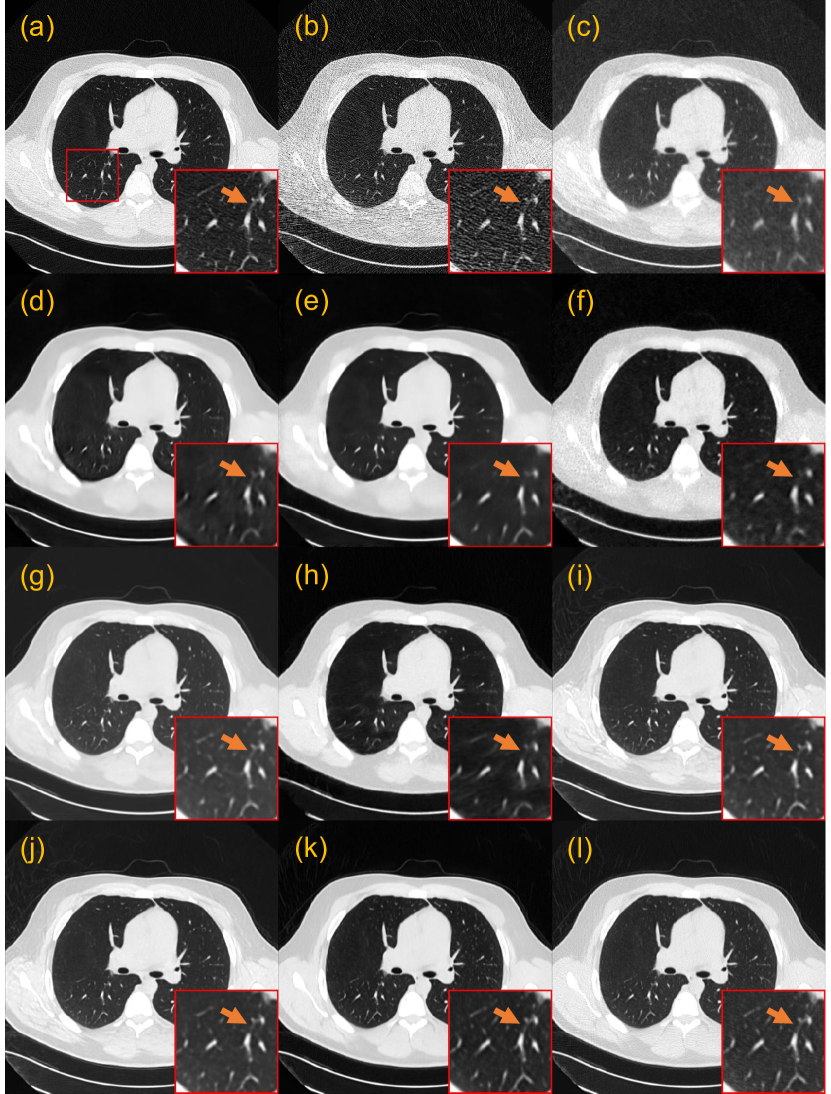

3.5.2 Generalization to the Mayo 2020 dataset

We further evaluated the effectiveness of the proposed CoreDiff and CoreDiff+OSLu on the 25% and 10% doses from the Mayo 2020 dataset. To simulate the clinical application scenario as closely as possible, we chose a chest slice of 5% dose and a abdomen slice of 25% dose, as well as their unpaired normal-dose slices, to train two one-shot models, respectively. By combining with these two separate one-shot models, we can quickly generalize our CoreDiff to mixed dose levels test data.

Fig. 11 presents the denoising results of a representative chest slice from Mayo 2020 dataset. All methods remove noise to some degree. RED-CNN-based methods smoothen the images, and the numerous details in the lungs were lost in the ROI. PDF-RED-CNN leads to some detail loss partially due to the gap between our incident photon number setting for 10% dose and the one used by Mayo Clinic. While PWLS preserves more information compared to RED-CNN-based methods, it may not provide sufficient noise reduction. Among the GAN-based methods, CNCL-U-Net performs best but also causes the offset of the background value. The diffusion-based methods exhibit a good trade-off between noise suppression and image fidelity. Finally, the proposed OSL framework is proven to be instrumental in enabling CoreDiff to achieve textures that closely resemble the ground truth.

Table 6 presents the quantitative results. Among the compared methods, PDF-RED-CNN has the highest PSNR, which benefits from the training with multiple doses of data, while IDDPM has the highest SSIM, indicating better preservation of the structural information. Surprisingly, our CoreDiff achieves better performance than them, even when trained only on 5% dose data without the additional OSL framework. We conjectured that this is due to the fact that a more reasonable diffusion-based method allows the model to progressively remove noise from the image and avoid structural distortion. In addition, the contextual error modulation module makes CoreDiff more robust to variation of inputs. The OSL framework further improves PSNR and SSIM, indicating that the CoreDiff+OSLu can produce more visually realistic texture and structural information by learning an optimal denoised image.